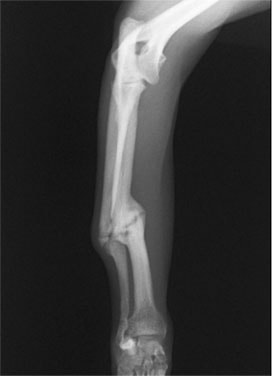

症例3:キルシュナーワイヤーのピンニングによる整復

ペルシャ猫 11ヶ月齢 雄

他院にて左大腿骨遠位の成長板骨折(salter-harrisⅠ型)が認められており、治療相談を目的として来院。当院にて、キルシュナーワイヤーを用いたピンニングにより骨折部位の整復を行いました。術後の経過は良好で、現在も経過観察中です。

術前レントゲン

術後レントゲン